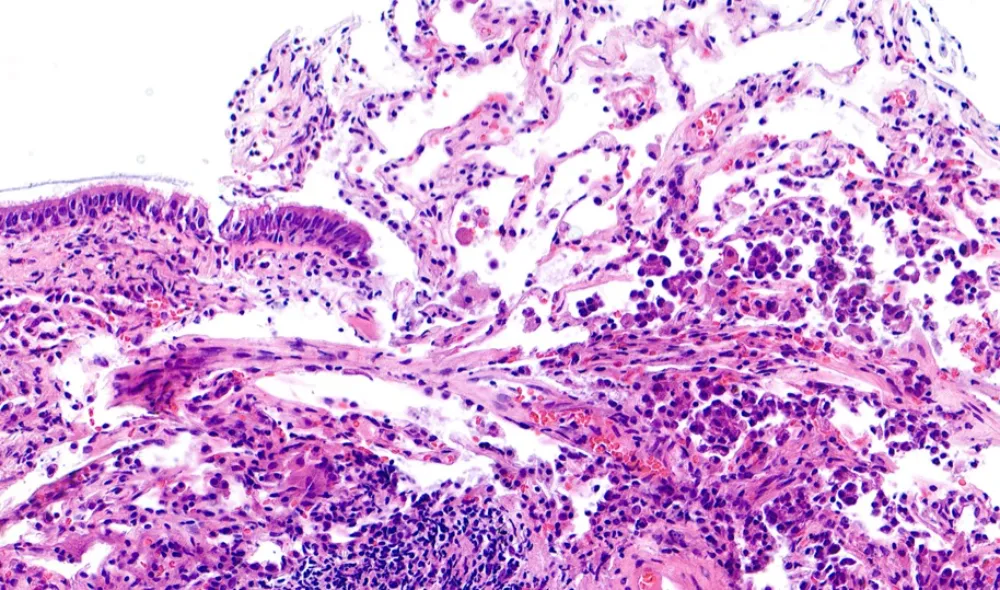

5-HE 1. Biopsia bronquial

- La biopsia bronquial evidencia grupos celulares que se “descaman” hacia los espacios alveolares, sin observarse tumor infiltrante.